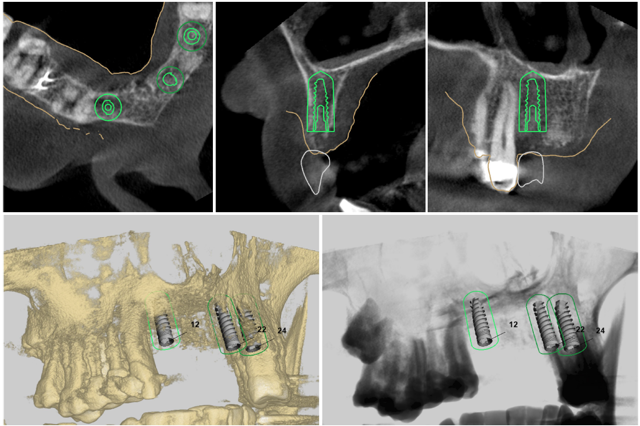

3D 列印技術,是讓數位牙科真正走向臨床的一大突破。其中典型案例是植牙導引板:結合口掃與斷層掃描資料,模擬未來重建後的假牙外型,設計出符合骨骼結構的植體角度,最後再由 3D 列印完成導引板。使植體在手術時可以依照原本設計的角度及位置植入,避開神經血管等重要組織,大大提升手術效率與安全性。